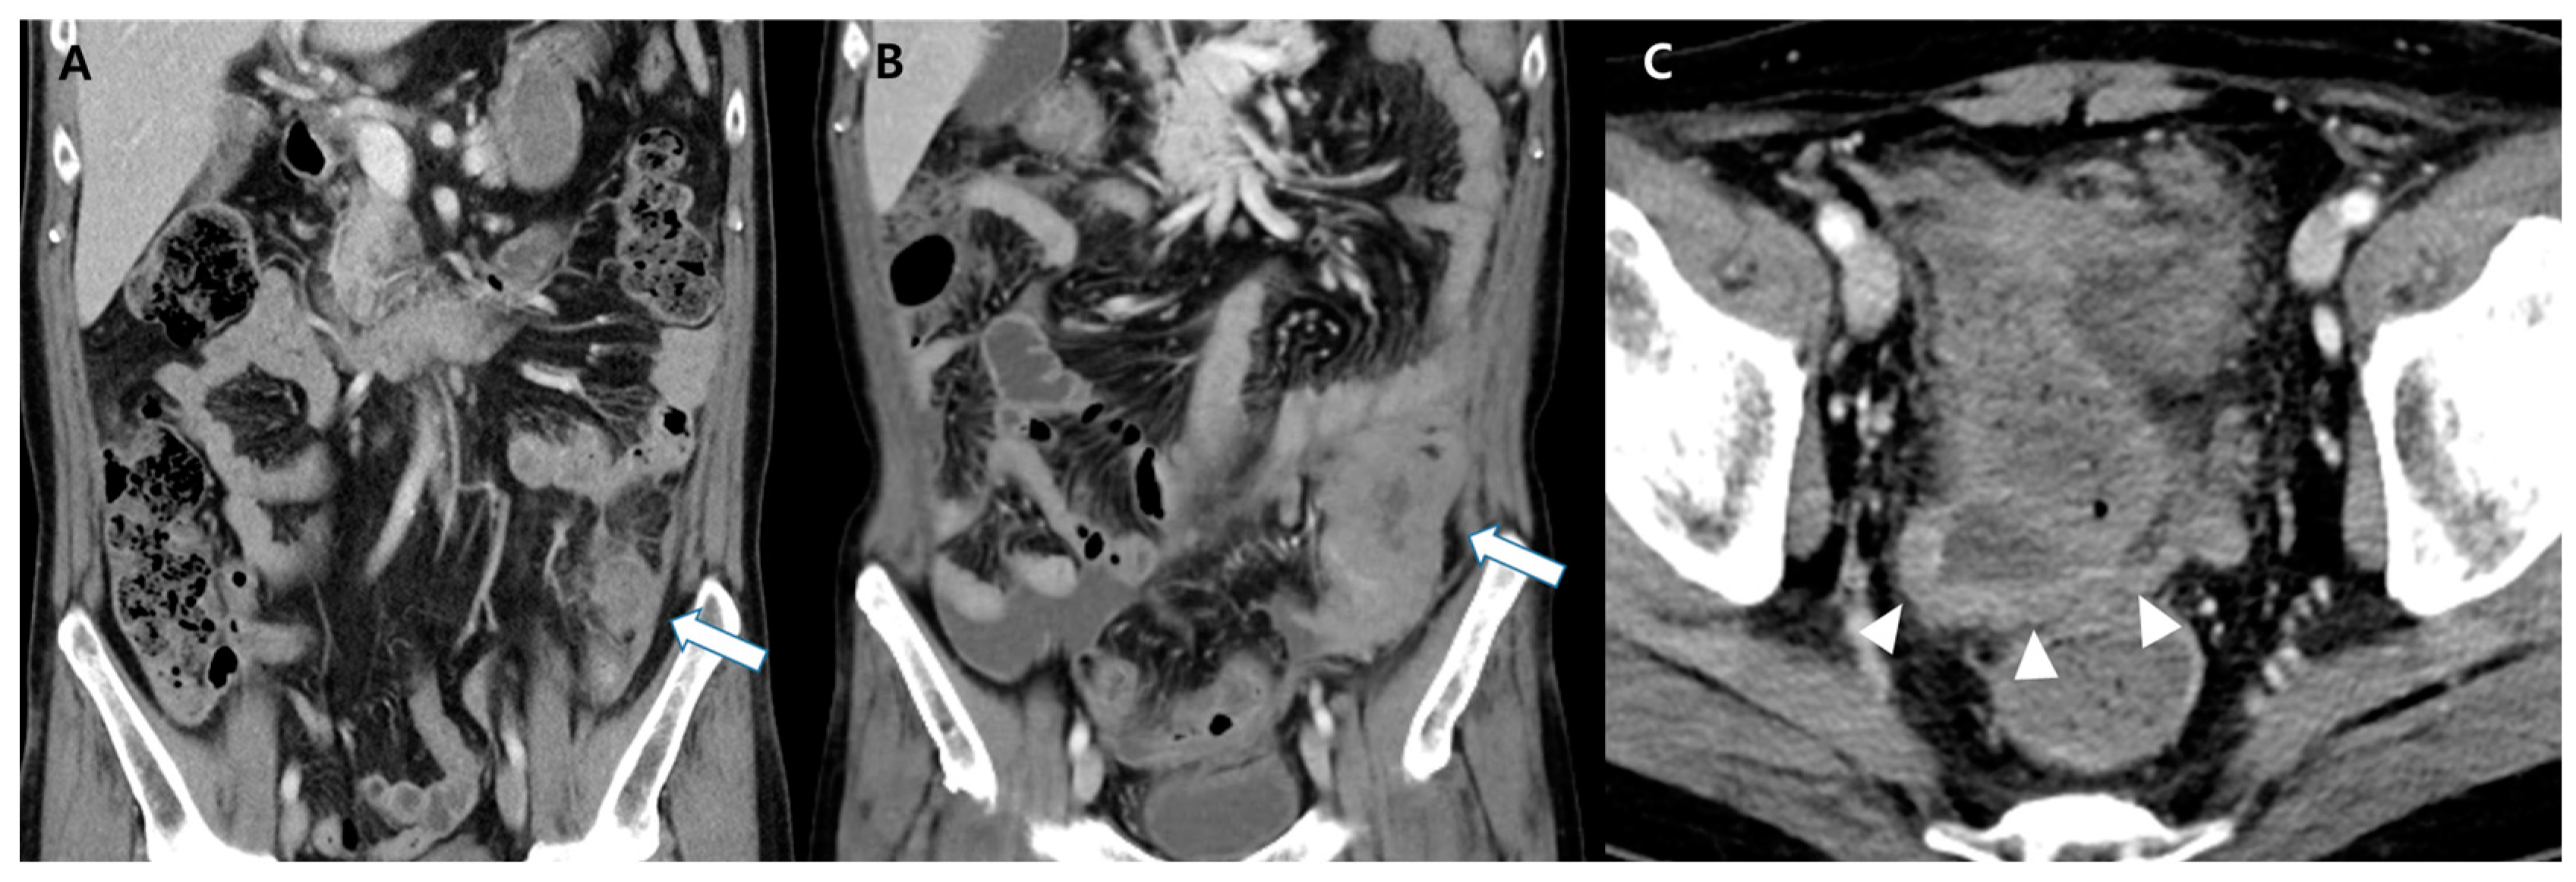

A 49-year-old man presented with intermittent, dull pain in the left lower quadrant of the abdomen for ten days. He visited our emergency room because of worsening symptoms. He had a history of acute myeloid leukemia (AML) with monosomy of chromosome 6, translocation between chromosomes 6 and 17, mono-allelic loss of TP53, and no commonly known molecular mutation 22 months previously. The initial diagnosis of AML was established through complete blood count (CBC) with differential, electrolytes, coagulation tests, flow cytometry immunophenotyping, and bone marrow histochemical staining. CBC revealed an elevated white blood cell count of 68.2 × 109/L, predominantly composed of blasts, decreased hemoglobin (7.8 g/dL), and low platelet count (42 × 109/L). Electrolyte levels and coagulation test results were within normal limits (INR 1.06). Flow immunophenotyping was positive for CD13, CD33, CD34, CD 64, and CD117, with partial HLA-DR expression. Bone marrow aspirate and biopsy confirmed hypercellular marrow with greater than 90% cellularity, predominantly composed of blasts. Histochemical staining was positive for myeloperoxidase and negative for Periodic acid-Schiff, confirming the myeloid lineage of leukemic cells. For the initial treatment of AML, the patient underwent induction chemotherapy with cytarabine (100 mg/m2, continuous infusion over seven days) and idarubicin (12 mg/m2 on days 1–3). After achieving complete remission, the patient received consolidation chemotherapy with high-dose cytarabine (3 g/m2 every 12 h on days 1, 3, and 5). The patient subsequently underwent allogeneic peripheral blood stem cell transplantation from an HLA-matched unrelated donor. No second induction chemotherapy was required prior to transplantation. Following allogeneic peripheral blood stem cell transplantation, the patient developed a chronic graft-versus-host disease affecting the skin, gut, and eyes, which was managed with immunosuppressive therapy. Physical examination revealed left lower abdominal tenderness. In addition to abdominal pain, the patient reported episodes of non-bloody diarrhea and occasional nausea, which did not respond to standard symptomatic gastrointestinal treatment. The patient did not report any constitutional symptoms, such as fever, night sweats, or unexplained weight loss, at the time of initial presentation or during the course of the disease. Laboratory studies showed mild elevation of C-reactive protein (5.35 mg/dL) and erythrocyte sedimentation rate (38 mm/h). Computed tomography (CT) revealed a 3 cm rim-enhancing fluid collection with adjacent inflammatory changes in the juxta-descending colon (Figure 1A). Colonoscopy yielded negative results, but a paracolic abscess was suspected based on the CT findings. After treatment with antibiotics, the pain resolved within 24 h. After five weeks, the patient returned due to progressively worsening abdominal pain. Physical examination revealed a hard, palpable mass in the left lower abdomen and diffuse abdominal tenderness. The patient was afebrile, with stable vital signs. Laboratory studies showed elevated C-reactive protein (11.95 mg/dL). Subsequent CT revealed an 8 cm enhancing soft tissue mass with perilesional fat infiltration involving the descending colon (Figure 1B). Additionally, a small amount of ascites with nodular peritoneal thickening was observed (Figure 1C). No bowel obstruction was caused by the large mass.

Figure 1. (A) Initial contrast-enhanced computed tomography image. This image shows rim-enhancing fluid collection with adjacent inflammatory changes localized in the juxta-descending colon, mimicking a paracolic abscess (arrow). (B) Follow-up scans obtained five weeks later. This follow-up image demonstrates the rapid and unexpected development of a large soft-tissue mass (arrow) in the descending colon (previously the site of the suspected abscess). Additionally, a small amount of ascites with nodular peritoneal thickening was observed (arrowheads). This finding prompted further investigations. (C) Additionally, a small amount of ascites with nodular peritoneal thickening was observed (arrowheads). This finding prompted further investigations.